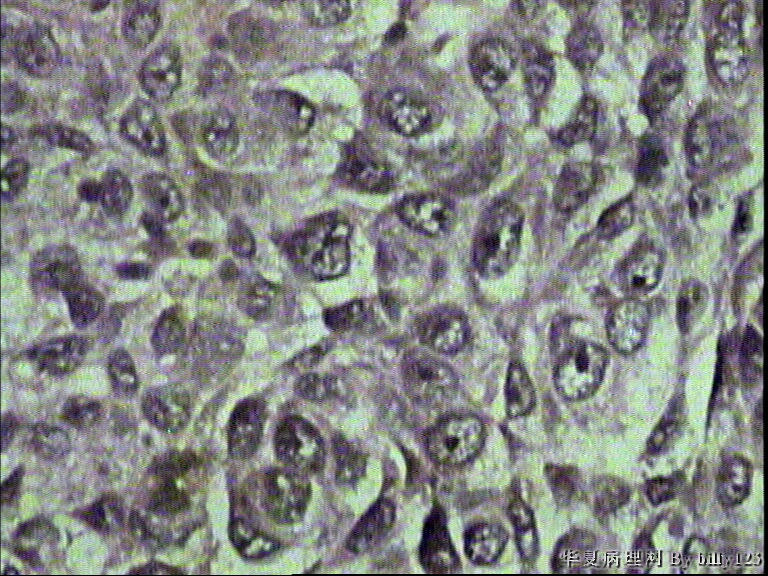

支气管活检,患者,男性,66岁,支气管镜下见息肉样新生物,鳞癌吗?请各位老师指教!

• 支气管活检,患者,男性,66岁,支气管镜下见息肉样新生物,鳞癌吗?请各位老师指教!图3

图3

棘层松解型鳞癌

从第二,三张图片的组织结构是鳞癌

鳞状上皮重度不典型增生,局部可疑浸润。

如果全面观察过切片确实没有浸润,可诊断为原位鳞癌。

全层有不典型增生 有坏死 考虑鳞癌